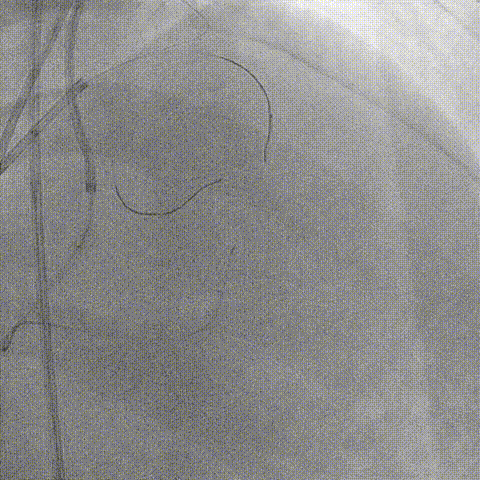

Ballon 2.5*15mm, 3.0*15mm Dilatation & IVUS check

LAD pre-IVUS check RUN 2

LAD Stent Synergy 3.5*38mm

Ballon QM 4.0*12mm, 5.0*8mm Dilatation & POT

LAD post-IVUS check RUN 3

Final result: TIMI flow grade 3